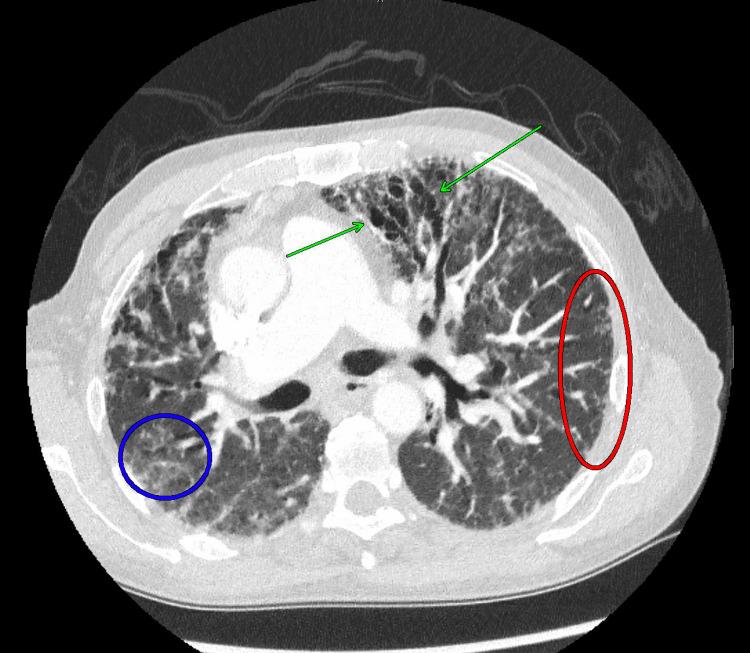

Histoplasmosis, a fungal infection caused by the inhalation of conidia spores, has been shown to cause disseminated disease in immunocompromised individuals. Disseminated histoplasmosis manifests as multi-system involvement including pulmonary and/or neurological disease. Imaging findings, such as pulmonary focal infiltrates, cavitary nodules, mediastinal, and hilar lymphadenopathy, are common. Here, we report a rare case of disseminated histoplasmosis in a 58-year-old immunocompetent male with no occupational exposure. This patient presented with primary adrenal insufficiency, and a subsequent CT-guided biopsy of the adrenal gland was performed and revealed numerous spores containing . This patient also suffered from numerous pulmonary and neurological derangements, which are likely sequelae of the disseminated fungal infection. Ultimately, the patient succumbed to their illness and died. Preventing such outcomes relies on early detection and prompt management, which are crucial in treating disseminated histoplasmosis. Increased awareness of atypical presentations can enhance patient outcomes and alleviate the impact of this severe fungal infection. This case not only underscores the importance of considering disseminated histoplasmosis in an immunocompetent patient presenting with unexplained weight loss and adrenal insufficiency but also contributes to the limited literature on disseminated histoplasmosis in immunocompetent individuals.

组织胞浆菌病是一种因吸入分生孢子而引起的真菌感染,已被证明会在免疫功能低下的个体中引发播散性疾病。播散性组织胞浆菌病表现为多系统受累,包括肺部和/或神经系统疾病。影像学表现,如肺部局灶性浸润、空洞性结节、纵隔和肺门淋巴结肿大,较为常见。在此,我们报告一例罕见的播散性组织胞浆菌病病例,患者为一名58岁免疫功能正常的男性,无职业暴露史。该患者出现原发性肾上腺功能不全,随后进行了CT引导下的肾上腺活检,结果显示有大量含孢子的组织。该患者还患有多种肺部和神经系统紊乱,这可能是播散性真菌感染的后遗症。最终,患者因病死亡。预防此类后果依赖于早期发现和及时治疗,这对治疗播散性组织胞浆菌病至关重要。提高对非典型表现的认识可以改善患者预后,减轻这种严重真菌感染的影响。该病例不仅强调了在出现不明原因体重减轻和肾上腺功能不全的免疫功能正常患者中考虑播散性组织胞浆菌病的重要性,也为免疫功能正常个体播散性组织胞浆菌病的有限文献增添了内容。